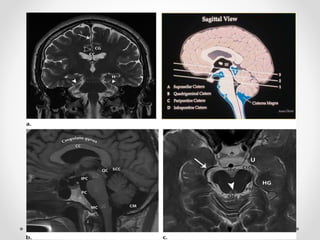

3. Thoát vị hạnh nhân

- Hạnh nhân tiểu não xuống thấp so với lỗ chẩm

=> Thân não hạ thấp, trung tâm hô hấp và tim mạch bị đè

ép vào bản dốc xương chẩm

- Nguyên nhân: giai đoạn sau của DTH, tăng áp lực hố

sau, chọc dò tuỷ sống dẫn lưu dịch não tuỷ...

CĐHA:

• Hạnh nhân tiểu não trở nên dẹt, nhọn, lồi xuống >3 mm

so với đường McRae line (tuỳ tác giả)

• Xoá bể lớn

• Ứ nước não thất do chèn vào não thất IV

• Nhồi máu tiểu não nếu chèn ép ĐM tiểu não sau dưới

3. Thoát vịhạnh nhân - Hạnh nhân tiểu não xuống thấp so với lỗ chẩm => Thân não hạ thấp, trung tâm hô hấp và tim mạch bị đè ép vào bản dốc xương chẩm - Nguyên nhân: giai đoạn sau của DTH, tăng áp lực hố sau, chọc dò tuỷ sống dẫn lưu dịch não tuỷ... CĐHA: • Hạnh nhân tiểu não trở nên dẹt, nhọn, lồi xuống >3 mm so với đường McRae line (tuỳ tác giả) • Xoá bể lớn • Ứ nước não thất do chèn vào não thất IV • Nhồi máu tiểu não nếu chèn ép ĐM tiểu não sau dưới